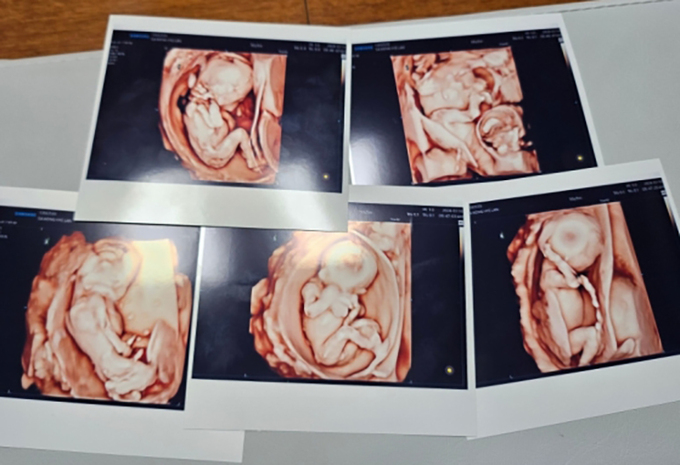

국내에서 임신부가 자연임신으로 생긴 다섯 쌍둥이를 분만한 첫 사례다. 국내에서 다섯 쌍둥이가 태어난 것은 지난 2021년 서울대병원 이후 약 3년 만이다.

가톨릭대학교 서울성모병원 산부인과 홍수빈·소아청소년과 윤영아·신정민 교수팀은 30대 산모가 다섯 쌍둥이를 건강하게 출산했다고 20일 밝혔다.

대학 시절 커플이 된 후 결혼에 이른 30대 부부는 다행히 빨리 찾아온 아가에게 ‘팡팡이’라는 태명을 지어주었다. 이후 단태아가 아닌 다섯 쌍둥이로 확인되자 태명도 멤버 5명의 활약상을 담은 드라마 ‘파워레인저’에 빗대어 ‘팡팡레이저’가 됐다.